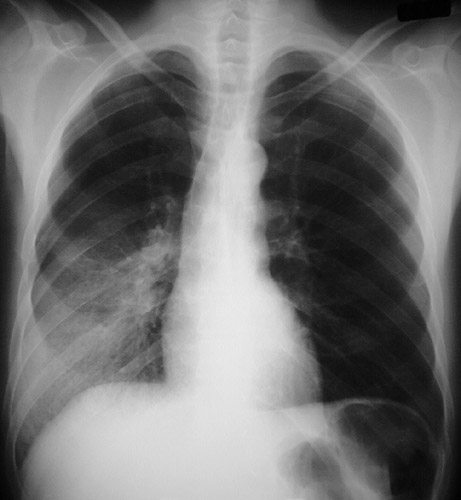

| The PA chest radiograph above demonstrates areas of opacification occupying the lower portion of the right lower lobe. The lateral view below reveals the infiltrates in this same area as well, consistent with a bronchopneumonia from a bacterial infection. (The bright vascular clips are from a previous abdominal surgery.) |